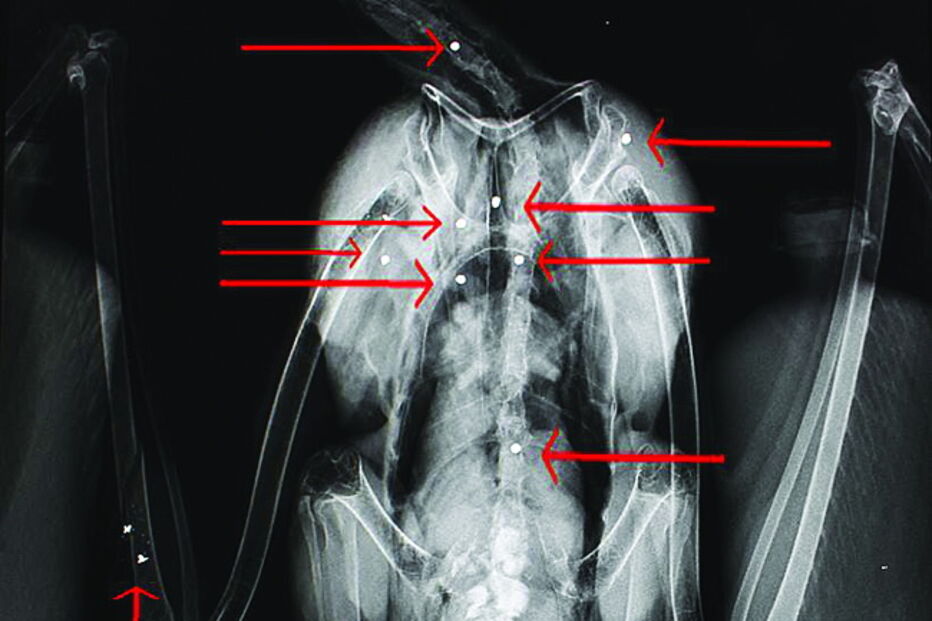

Os casos de maior sucesso foram uma cegonha, que tinha sido encontrada com 10 chumbos no corpo, e um falcão peregrino, atingido numa asa. Quanto às aves ainda em recuperação, tratam-se de três gaivotas, adianta o RIAS, que não especifica quais as espécies dos cinco animais que morreram em resultado de ferimentos sofridos.

A cegonha branca com 10 chumbos de caçadeira no corpo chegou ao RIAS a 12 de abril. Foi devolvida à natureza, no início do mês, recuperada. Tinha um ovo, parcialmente afetado, que foi expulso.